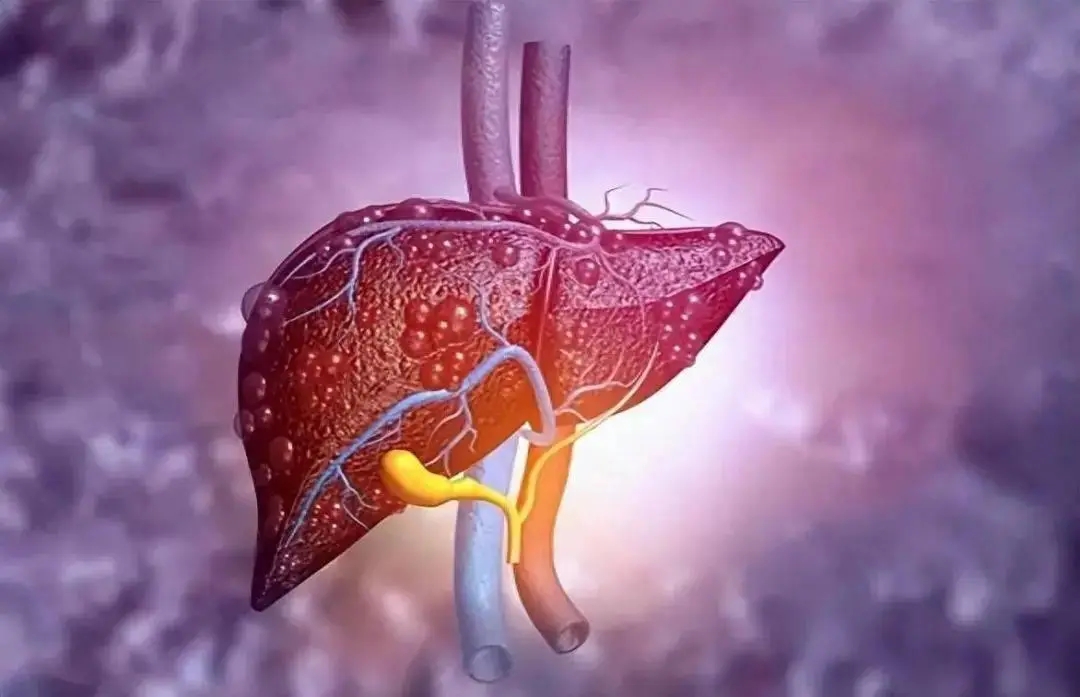

颠覆认知!华科大揭示肝癌进展新机制,开辟精准诊疗双通道

新型抑制剂!郑州大学/华东师范大学合作发文:可提高肝癌治疗效果的联合治疗策略